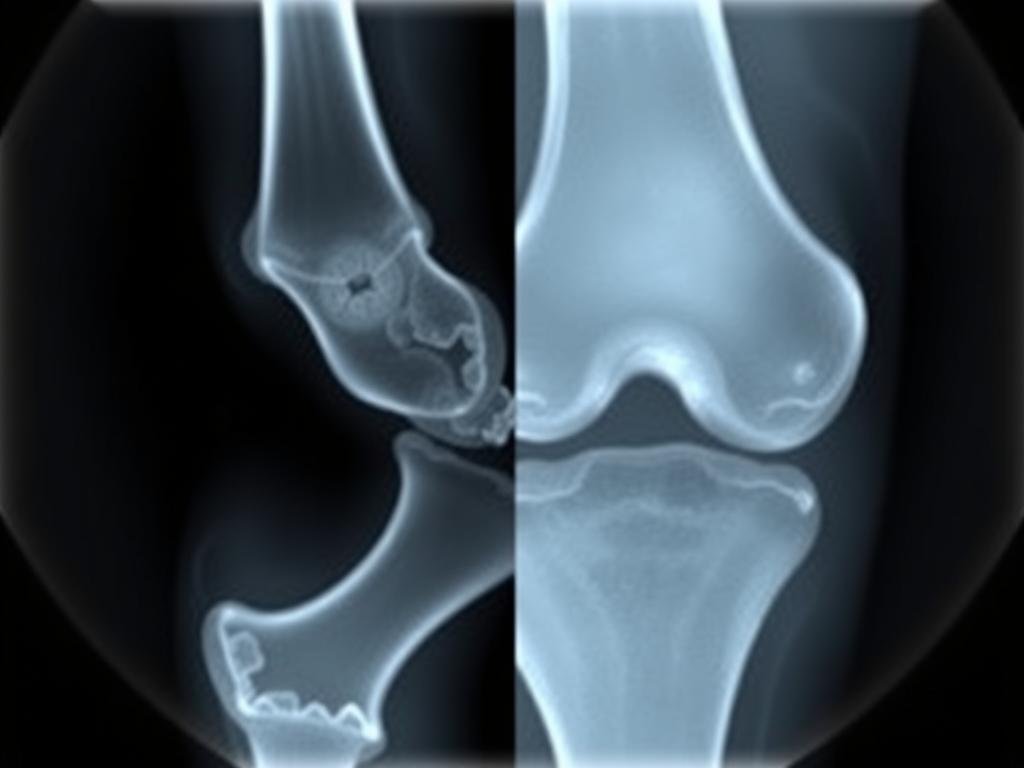

Diagnose der Arthrose

Eine präzise Diagnose ist entscheidend für die Wahl der richtigen Behandlungsstrategie. In unserer orthopädischen Praxis setzen wir auf eine umfassende Diagnostik:

Röntgenbild eines von Arthrose betroffenen Kniegelenks mit deutlicher Gelenkspaltverengung

Moderne Diagnoseverfahren

Bildgebende Verfahren

Moderne Bildgebung ermöglicht einen detaillierten Blick ins Gelenkinnere:

- Röntgen: Zeigt Gelenkspaltverengung und Knochenveränderungen

- MRT: Stellt Knorpel, Bänder und Weichteile präzise dar

- CT: Liefert detaillierte Knochenbilder bei komplexen Fällen

- Ultraschall: Ermöglicht die Beurteilung von Entzündungen und Ergüssen